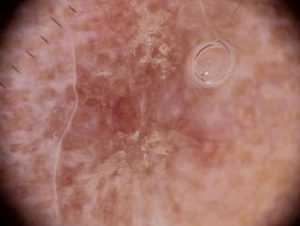

Рис. 1а. Актинический кератоз

Рис. 1б. Дерматоскопия актинического кератоза